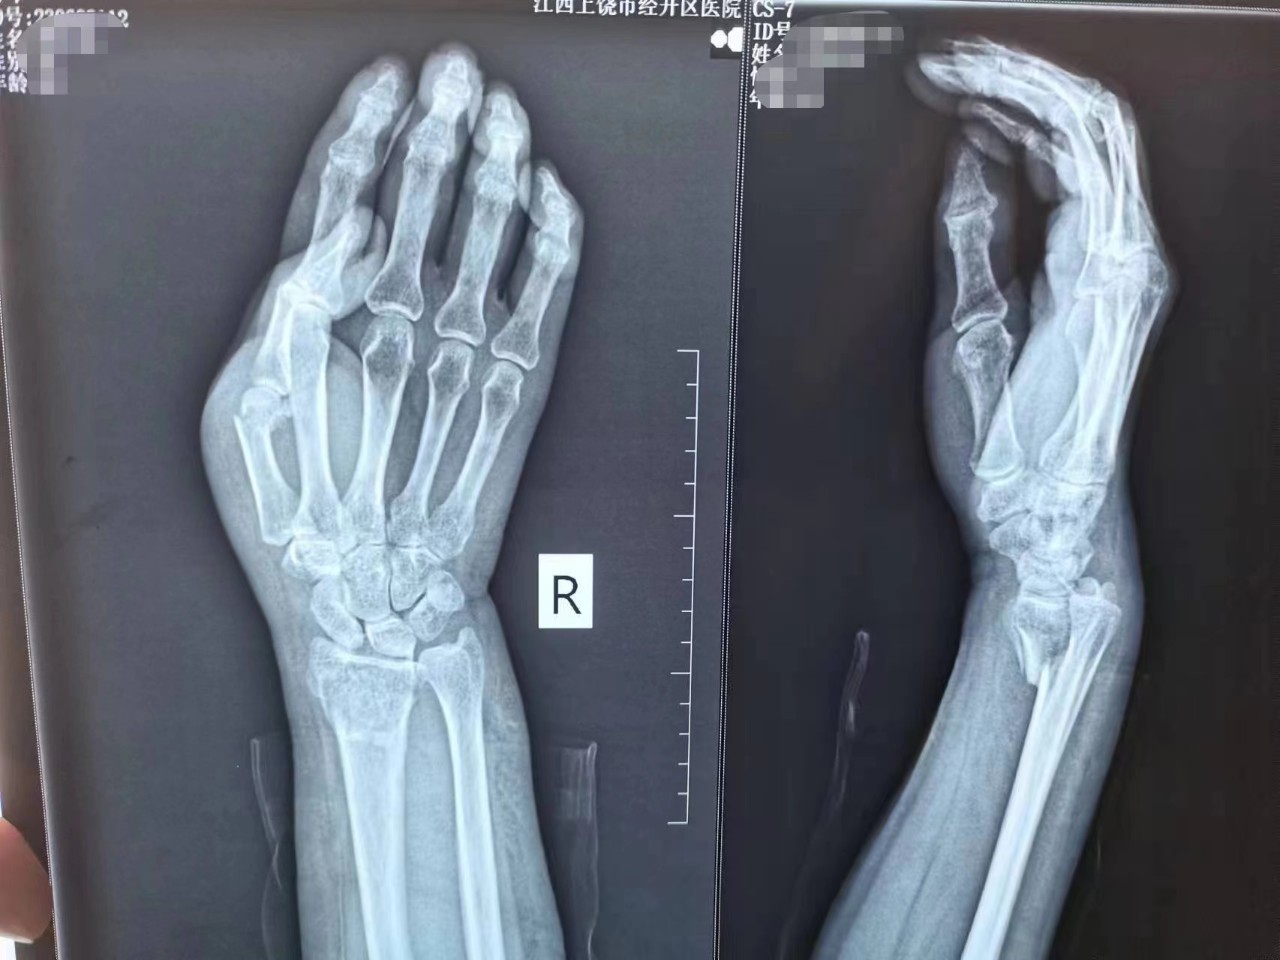

骨外科主任程广东医师亲自接诊,在仔细询问了顾奶奶的病史后,经CT及相关辅助检查诊断为“1.双侧桡骨远端骨折伴腕关节脱位 2.右侧第一掌骨骨折”。根据顾奶奶的病情及身体状况为顾奶奶量身制定手术方案,建议顾奶奶做两次手术来解决“双腕部骨折”问题。

当您在摔倒手或手腕撑地后,出现上述一种或多种症状后,就要高度怀疑发生了桡骨远端骨折。这个时候应抬高患肢,有条件者可使用硬纸板或书本平托手腕,避免下垂及活动,并及时前往医院就诊,通常通过X线片检查可以明确有无桡骨远端骨折,必要时需进一步行CT检查。